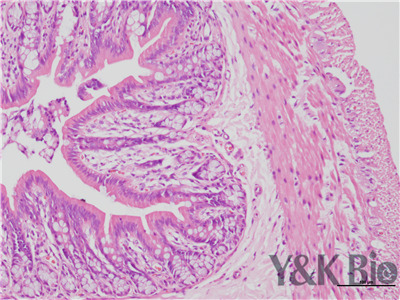

HE染色流程是什么,很多人都不知道,今天跟着小编一起来学习一下,切片的好坏直接影响疾病诊断的及时与准确性。因此一张高质量的HE染色切片,是实验室必须掌握的技术之一。HE染色目前在国内国外病理诊断上被

广泛采用,常规的染色方法。下面一起来看HE染色的基本顺序。一般切片的片子应在60-70度左右的烤箱中烘烤30分钟以才可以进行染色。总的来说是一个时间较长的过程。

1.样品制备

对于贴壁生长细胞,胰酶消化,调整细胞浓度约1×105/ml,滴加于盖玻片上(置于6孔板中),培养相应时间后,取出细胞爬片,用PBS 洗涤3次。2.样品固定 95%乙醇固定20min,PBS洗涤2次,每次1min。3.染核 苏木

素染液染色2-3min,自来水洗涤。4.分色 镜下观察,若细胞核染色过深,用1%盐酸酒精溶液分色数秒,自来水洗涤。 5.染胞质 浸入伊红染液染色1min,自来水洗涤。6.封片 吹干或自然晾干细胞爬片后,云南中性树胶封片。

以上六点就是HE染色的基本步骤,大家可以参考一下哦 。